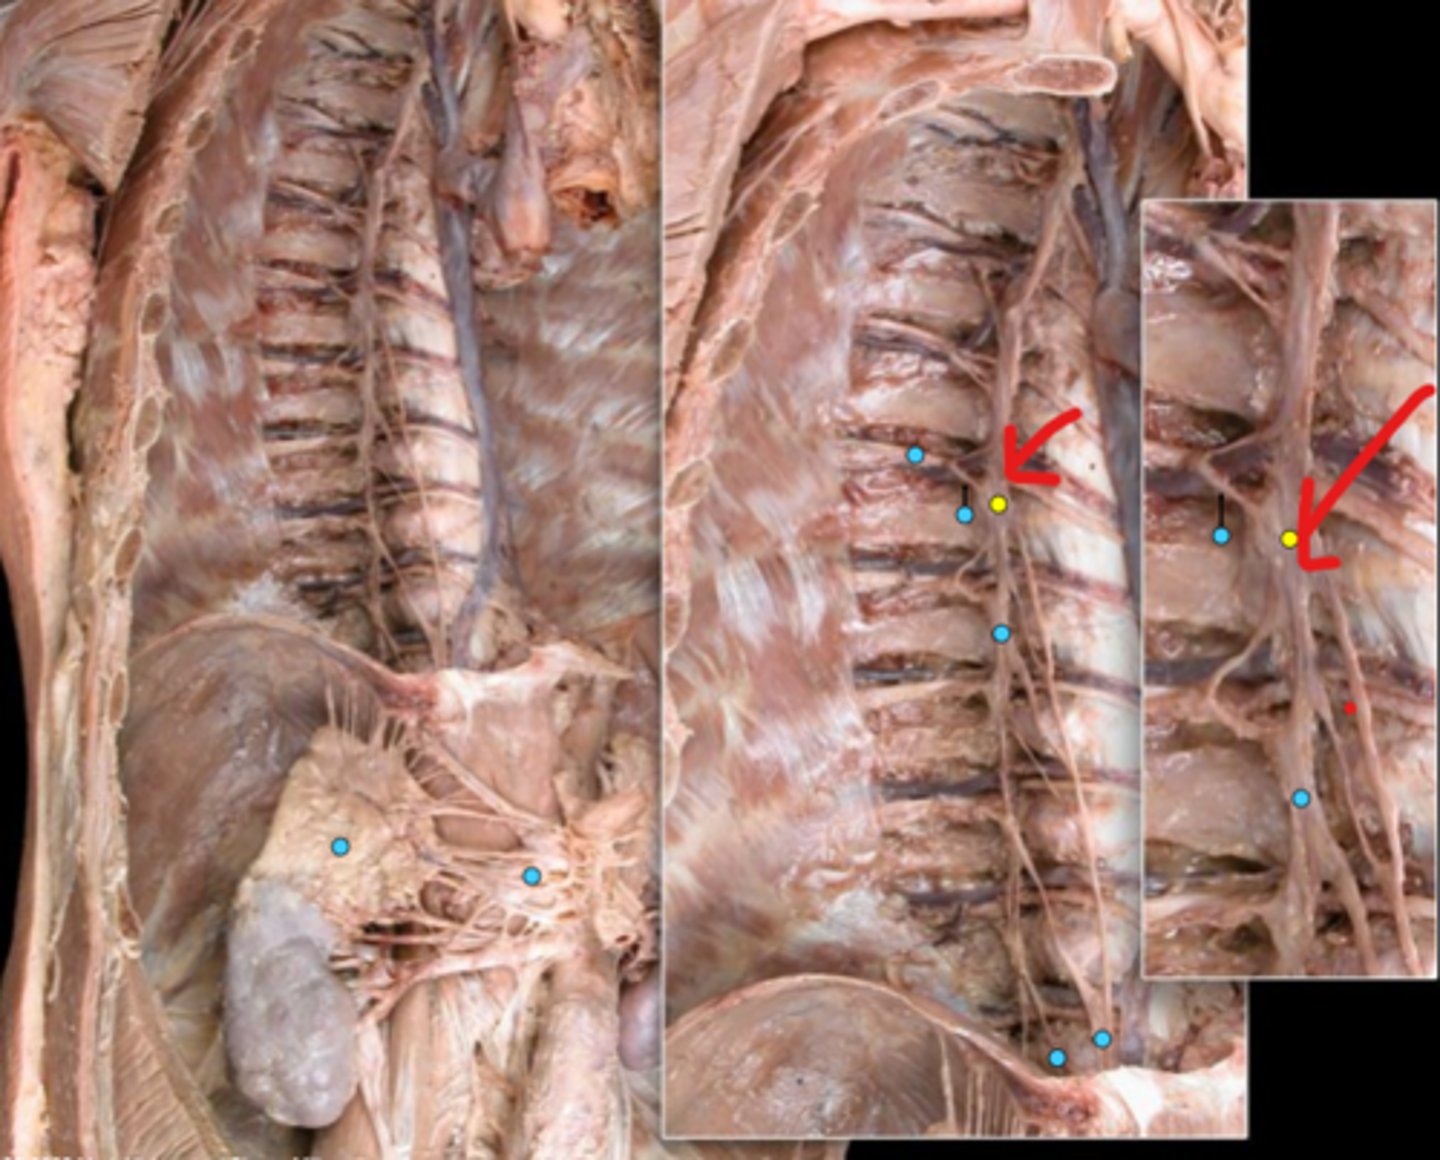

Suprarenal gland

Celiac ganglion

Intercostal nerve

Communicating ramus

Sympathetic trunk ganglion

Sympathetic trunk

Lesser splanchnic nerves

Greater splanchnic nerve

Anterior (ventral) ramus

Spinal nerve trunk

Posterior (dorsal) ramus

Spinal ganglion